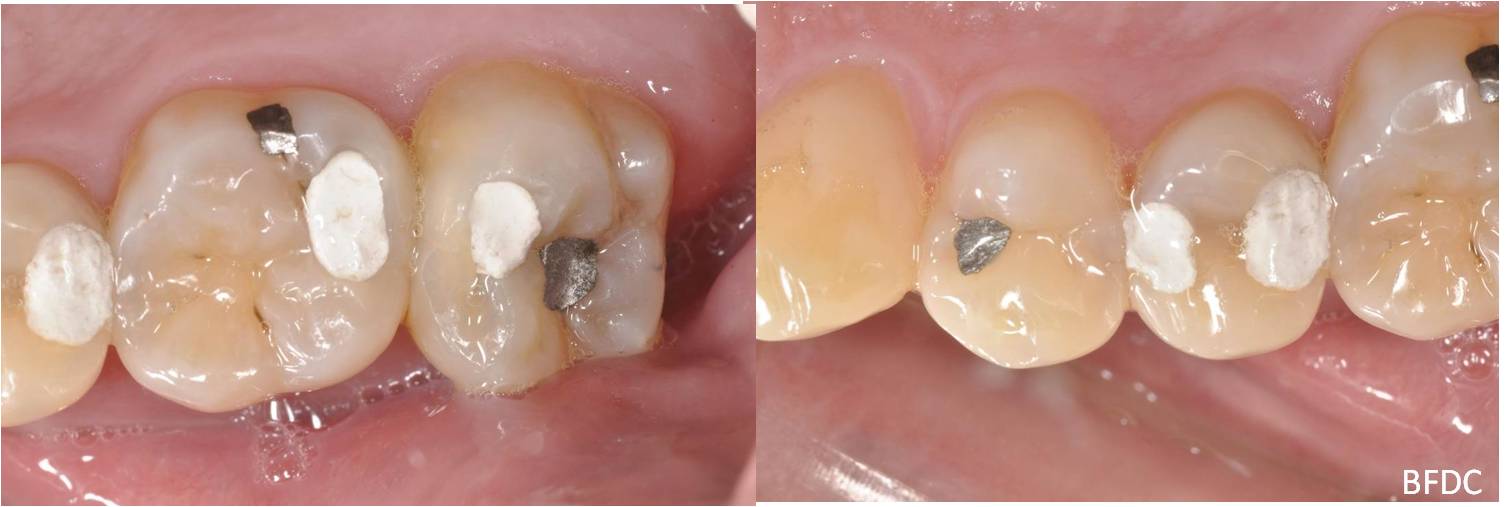

陶瓷崁體及冠蓋體-蛀牙-#1516172526 大範圍的補皮,該如何選擇,嵌體的方式就適用於大範圍的填補,因為它是一體成形, 嵌體材質多種,以往才會使用黃金合金,但因價格昂貴且顏色太過突出,因此現在多使用玻璃陶瓷二氧化鋯等材質的全瓷冠。嵌體有其優勢,因一體成形的材料,硬度和穩定性都較高,不用一點一點填補,減少下方凹陷重複蛀牙的危機,也不會變形或染色,美觀度高很多。 #1516172526蛀牙 #1516172526蛀牙 崁體及冠蓋體修形 安裝模型至咬合器 嵌體及冠塊體製作 陶瓷崁體及冠蓋體 黏著後 黏著後X光 術前、術後比較 嵌體有其優勢,因一體成形的材料,硬度和穩定性都較高,不用一點一點填補,減少下方凹陷重複蛀牙的危機,也不會變形或染色,美觀度高很多。

能避免片狀樹脂造成的,下方重複蛀牙,或彈性大造成咬合不舒服的問題,若有多顆牙齒填補,或坑陷較大者,如牙齒已蛀超過1/2或2/3者,才建議使用此種方式。